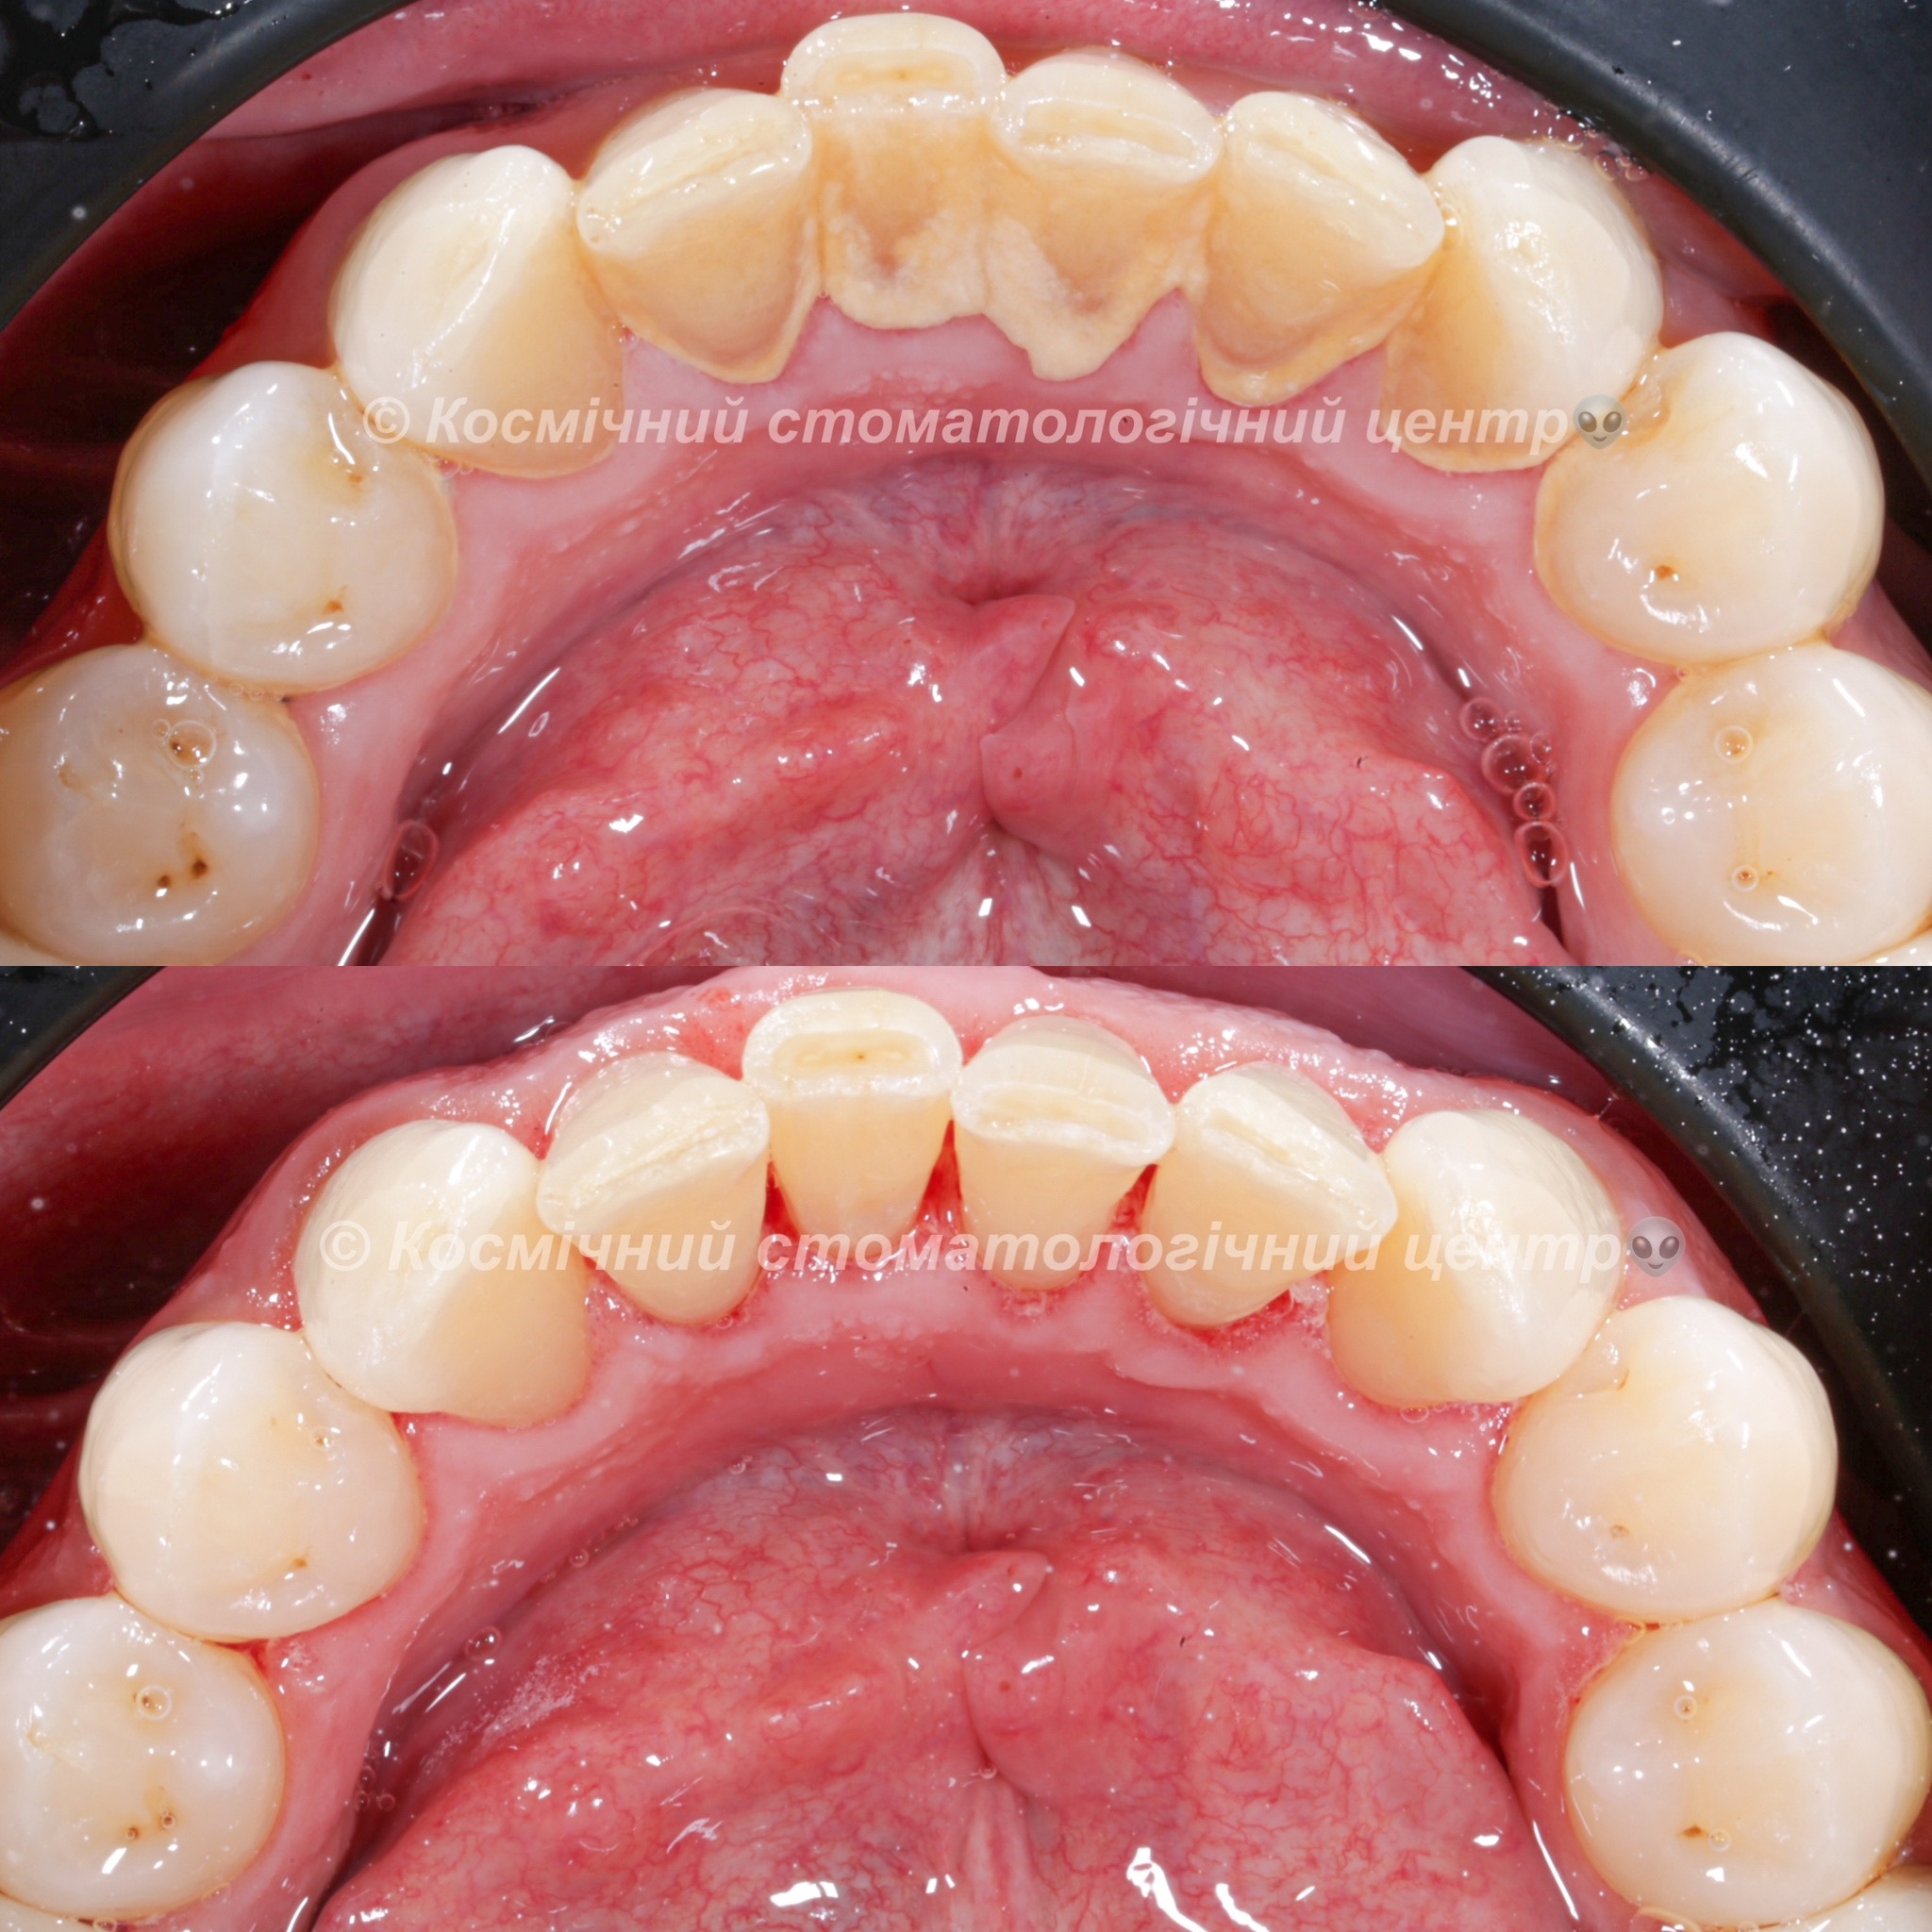

Галерея

Професійна гігієна (чистка) зубів складається з кількох етапів

Повітряно-абразивна чистка зубів (Air Flow)

Завдяки піскоструменевому апарату з технологією Air Flow, який використовуючи тиск повітря та води, подає на зубну емаль спеціальний абразивний склад, зуби можна очистити не лише від м’якого нальоту, а й від пігменту. Для видалення нальоту, в Космічній стоматології Драганчука ми використовуємо KaVo prophy pearls supragingival calcium carbonateneutral.

Чистка зубів щіточками та пастами

Фінальний етап професійної гігієни - полірування спеціальними щіточками та пастою, щоб усунути мікротріщини та шорохуватості, що виникли після чистки та видалити залишки нальоту, що могли в них залишитись. Це дозволяє суттєво уповільнити формування нових відкладень.